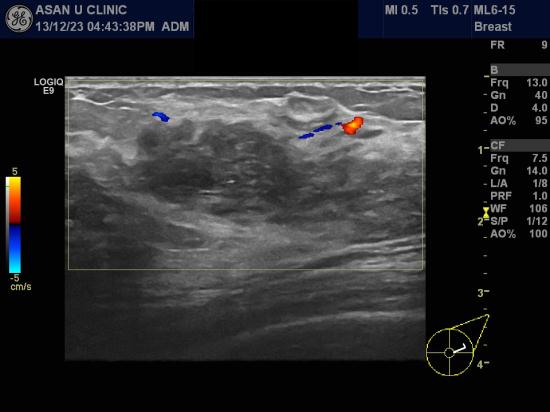

아산유외과 개원 후 49번째 유방암진단

건강검진상 이상소견으로 본원에 내원한 32세 여성분입니다.

좌측 유방 상외측에 미세석회화가 모여있으며

유방초음파상 유관확장 소견이 동반되어있어

조직검사를 시행하여 0기암인 상피내암 진단되었습니다.

어머니도 유방암으로 수술받으신 가족력이 있는 분입니다.

이처럼 가족력이 있다면 20 내지 30대의 여성분이시더라도

유방암 검진으로 확인하는 것이 좋습니다.